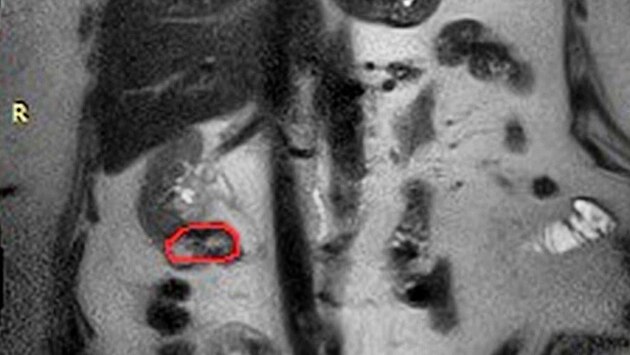

Врачи НОКБ имени Семашко провели сложную операцию и сохранили единственную почку 73-летней пациентки, у которой произошёл рецидив онкологического заболевания. Ранее женщине уже удалили левую почку, а также сделали частичную резекцию правой почки. Однако на плановом контрольном обследовании врачи выявили рецидив опухоли в оставшейся почке.

Специалисты онкологического отделения приняли решение о проведении органосохраняющей операции. Хирурги удалили опухоль, остановив кровообращение в почечных сосудах на семь минут, что позволило минимизировать риски осложнений. Операцию провела бригада онкохирургов: заведующий онкологическим отделением Марк Мамонов, врачи-онкологи Аркадий Осипов и Сергей Волков.